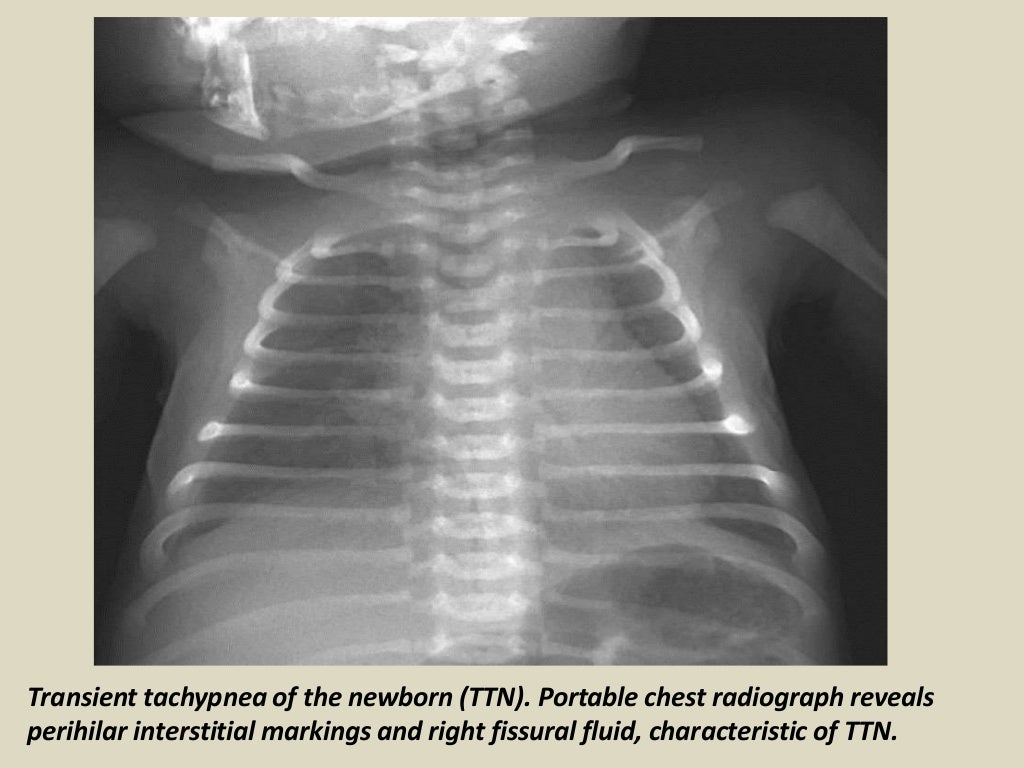

Transient tachypnea of the newborn wikidoc Rattling In Lungs Newborn It is worse when a child is lying on their back. Stridor is a type of noisy breathing. It's most common in babies because their airways are narrower. In fact, this condition is the most. Stridor usually indicates an obstruction or narrowing in the upper airway, outside of the chest cavity. It is caused by excess tissue around the larynx. Rattling In Lungs Newborn.

From learningradiology.com

LearningRadiology Transient, tachypnea, newborn, ttn Rattling In Lungs Newborn One of the main causes of noisy breathing, or stridor, is called laryngomalacia —a long name for a condition that usually is harmless. It's most common in babies because their airways are narrower. Newborn babies make these noises as they breathe (healthier together nd) your baby's tiny lungs and nose have only just started inhaling air. Stridor usually indicates an. Rattling In Lungs Newborn.